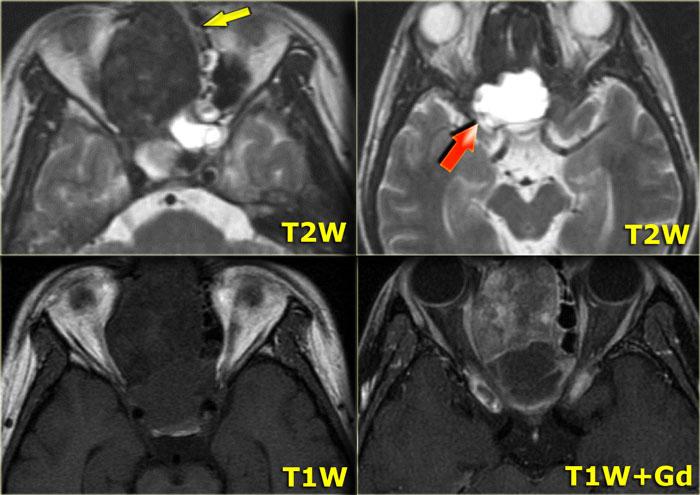

Hình ảnh bên trái của một bệnh nhân được nghi ngờ mắc u sụn ác tính (chondrosarcoma).

Trên chuỗi xung T2W, có một tổn thương giảm tín hiệu (mũi tên vàng) kèm thành phần dạng nang (mũi tên đỏ).

Trên chuỗi xung T1W trước và sau tiêm thuốc tương phản từ, khối u ngấm thuốc đồng nhất với vùng ngoại vi của thành phần nang ngấm thuốc theo chu vi.

Câu hỏi: bước tiếp theo cần thực hiện là gì?

Bước tiếp theo: chụp CT!

Trên CT, đây là hình ảnh loạn sản xơ (FD) điển hình với vỏ xương còn nguyên vẹn và hình ảnh kính mờ (ground-glass).

Nhiều tổn thương loạn sản xơ ở vùng clivus, nền sọ hoặc hốc xoang-mũi, đặc biệt ở trẻ em, có thể có thành phần nang lớn, vì vậy đừng để điều đó làm bạn phân vân trong chẩn đoán!